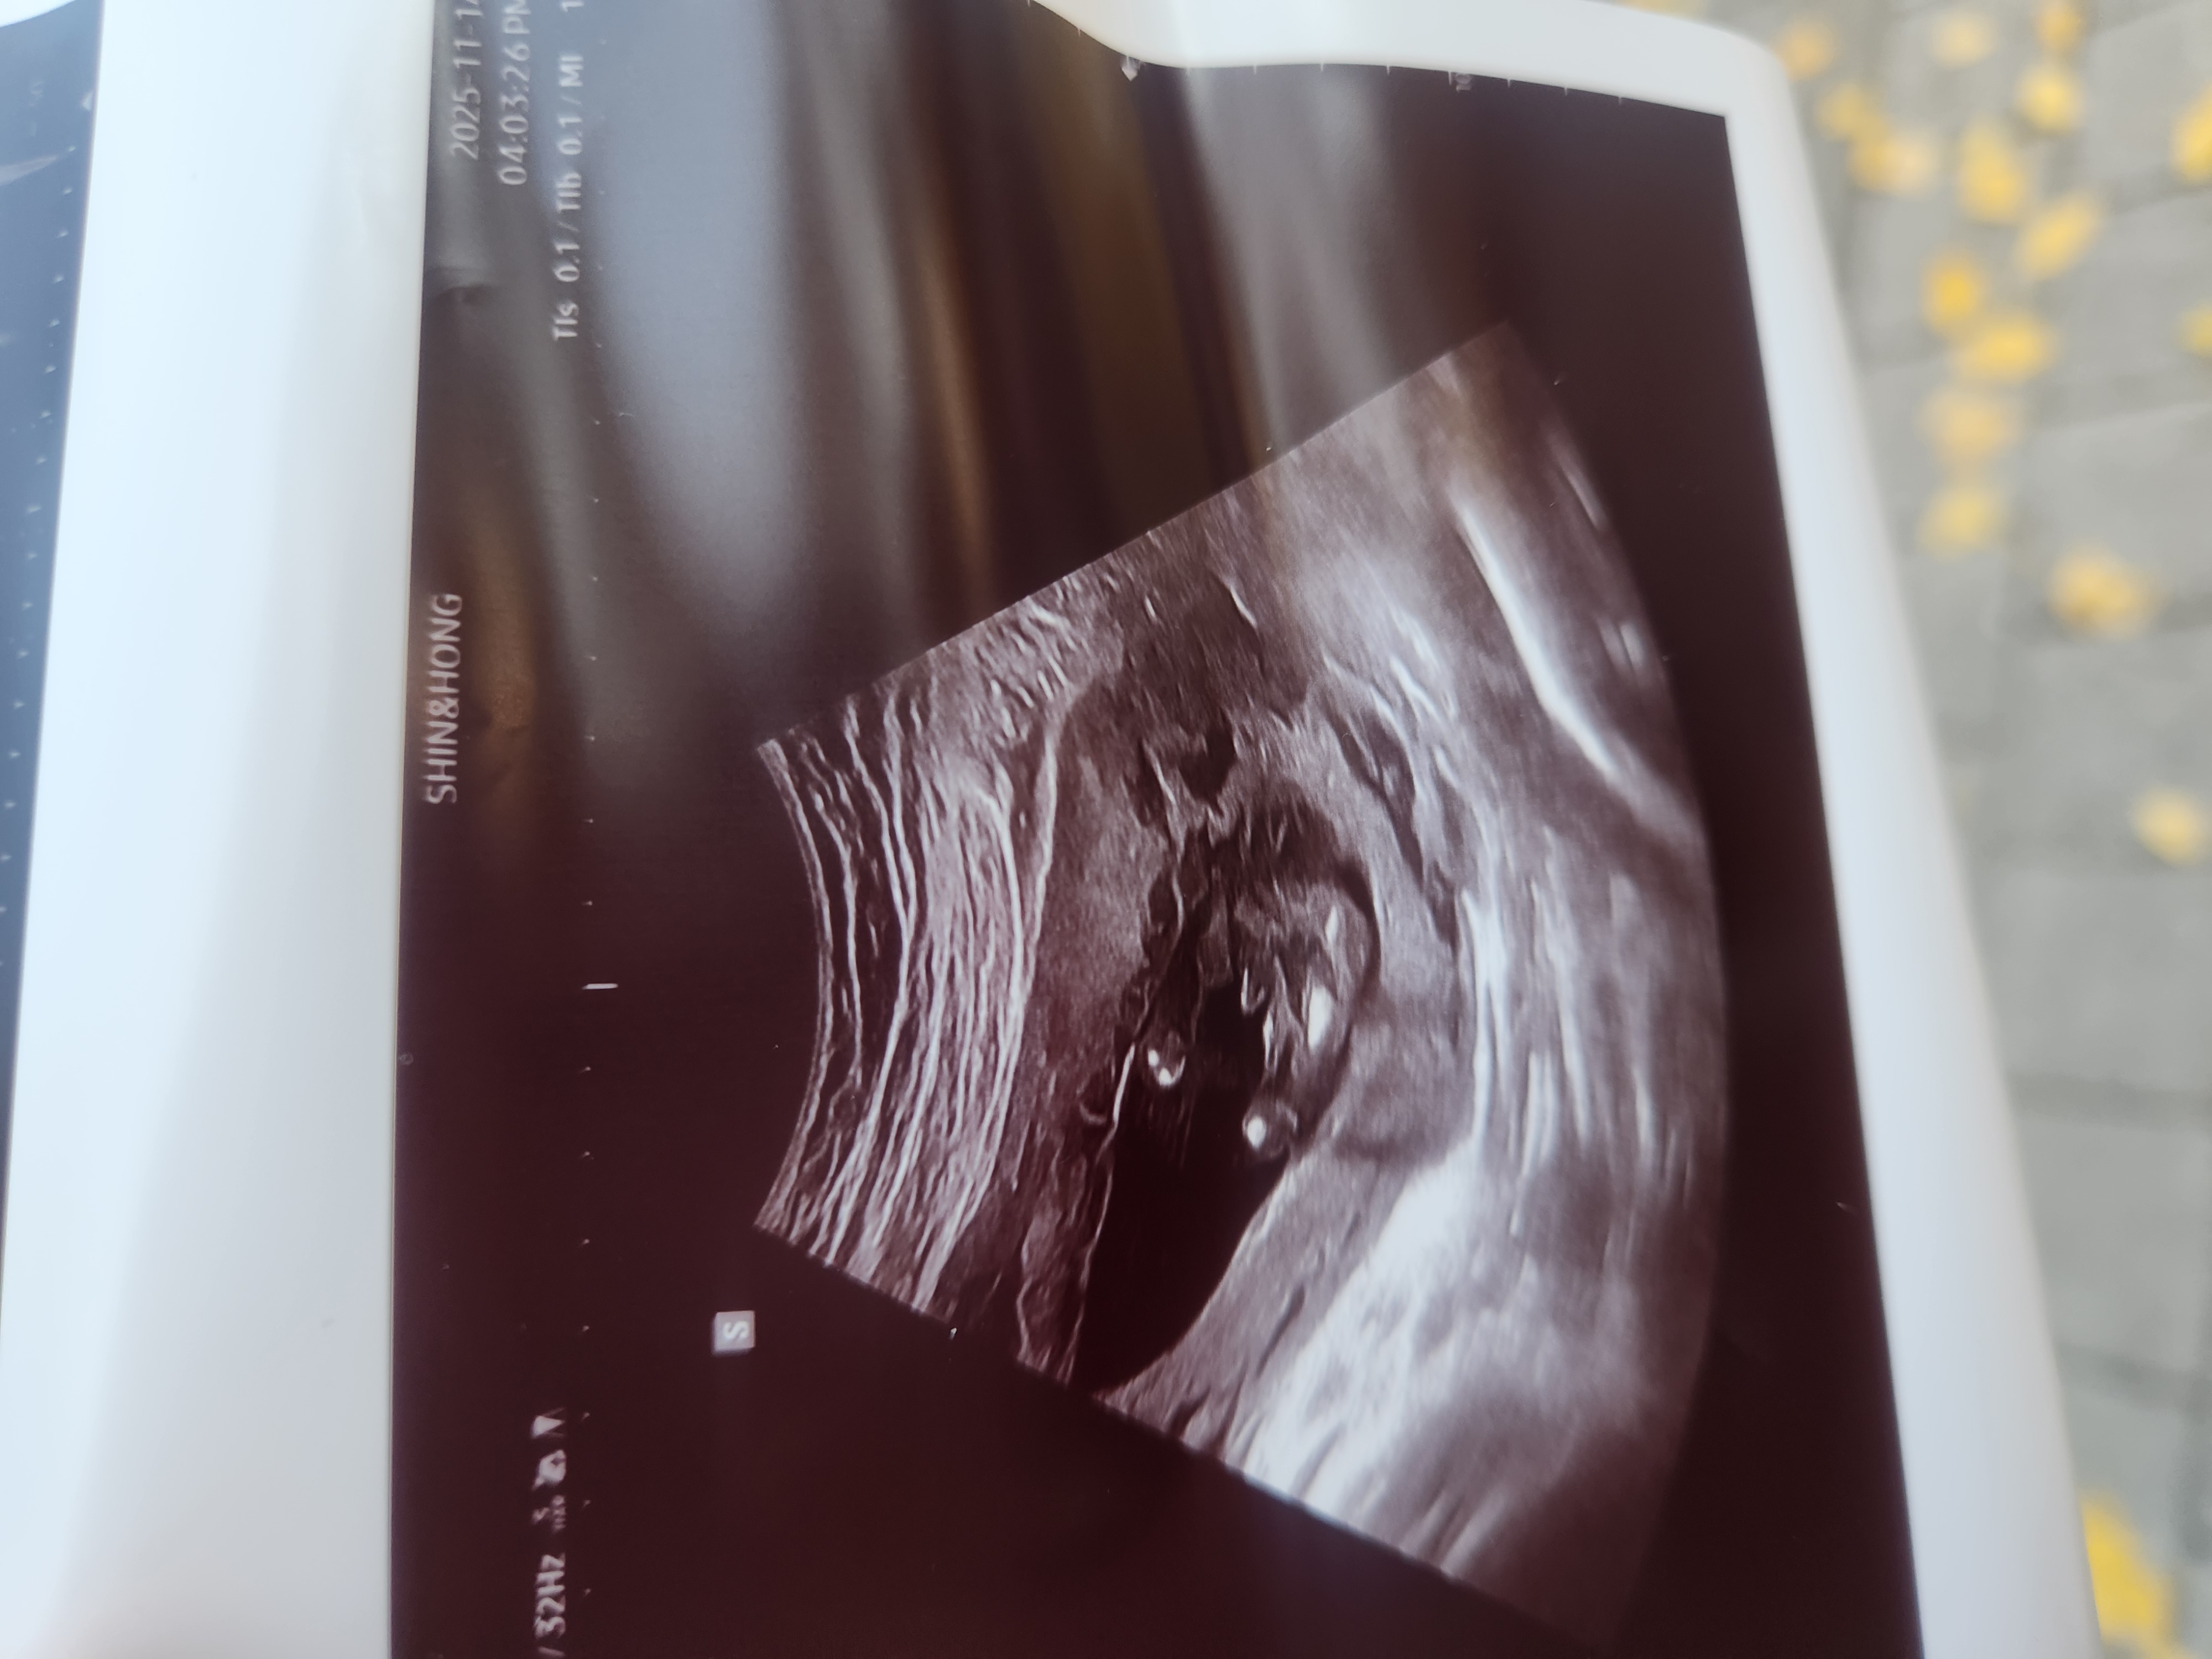

의사선생님은 담주에 다시 보자시는데

어때보여요???

확신의 아들같아보여요..!

아들인데용???

15주 5일요!